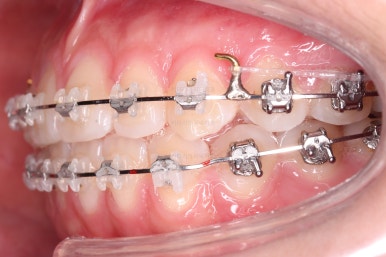

미니스크류를 이용해서 전체 치열을 움직인지 6개월 정도 지난 시점입니다.

교합도 많이 좋아졌고 자연스럽게 중앙선도 맞아졌어요.

미묘한 치열의 사이즈 문제라든지 턱뼈의 비대칭 때문에 맞지 않는 중앙선은 그대로 놔두기도 하지만 왠만하면 잘 맞도록 하는게 좋겠죠?

이제는 디테일한 마무리만 좀 더 하고 치료를 종료하기로 했습니다.

교합도 안정되는 것을 확인했고, 치열도 만족할 수준으로 디테일한 정리를 해줬어요.

왼쪽이 치료 초기의 교합 모습, 오른쪽이 치료 마무리 시점의 교합입니다.

빈틈이 많았던 교합이 많이 개선된 것이 보이시죠?

이러한 이유 때문에 전체교정이 필요했답니다.